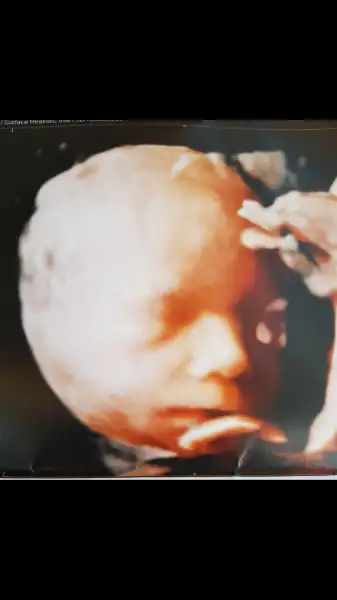

Gözün aydın canım,uykucu minik :) Tam uyuyacağı zamanmis görüşmeniz demek ki. Maşallah çok tatlı esniyorKizlar bugün kontrolümuz vardı herşey yolundaydı çok tatliydi ama yuzunu pek dönmedi bize esnedi 2 kere sonra birdaha göstermedi. Ben de videosunu cektim resim yakalayamadık. Doktor 2 ay sonra gel dedi. Hiç-bir sıkıntı görünmüyor öbür aya gelmene gerek yok hem 2 ay sonra yanakları dolar. Sana tombis resmini veririm dedi.

Iyiyiz çok şükür şeker testimiz de temiz..buda benim çektiğim resim esnerken. O zaman bile yüzünü göstermedi eliyle kapattı